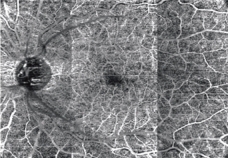

パノラマ自動合成機能

12×9mmの撮影範囲内で2種(3/4.5mm)のパノラマ合成を自動でおこなうことが可能です。

スキャン位置は順次移動するため、固視位置を変更することなく撮影できます。

任意設定により5種類(初期設定:網膜全層、表層、深層、外層、脈絡膜)のパノラマが同時に自動合成できます。

網膜全層 HD4 4.5×4.5mm 6枚 パノラマ |

網膜表層 |

網膜深層 |

網膜外層 |

脈絡膜 |